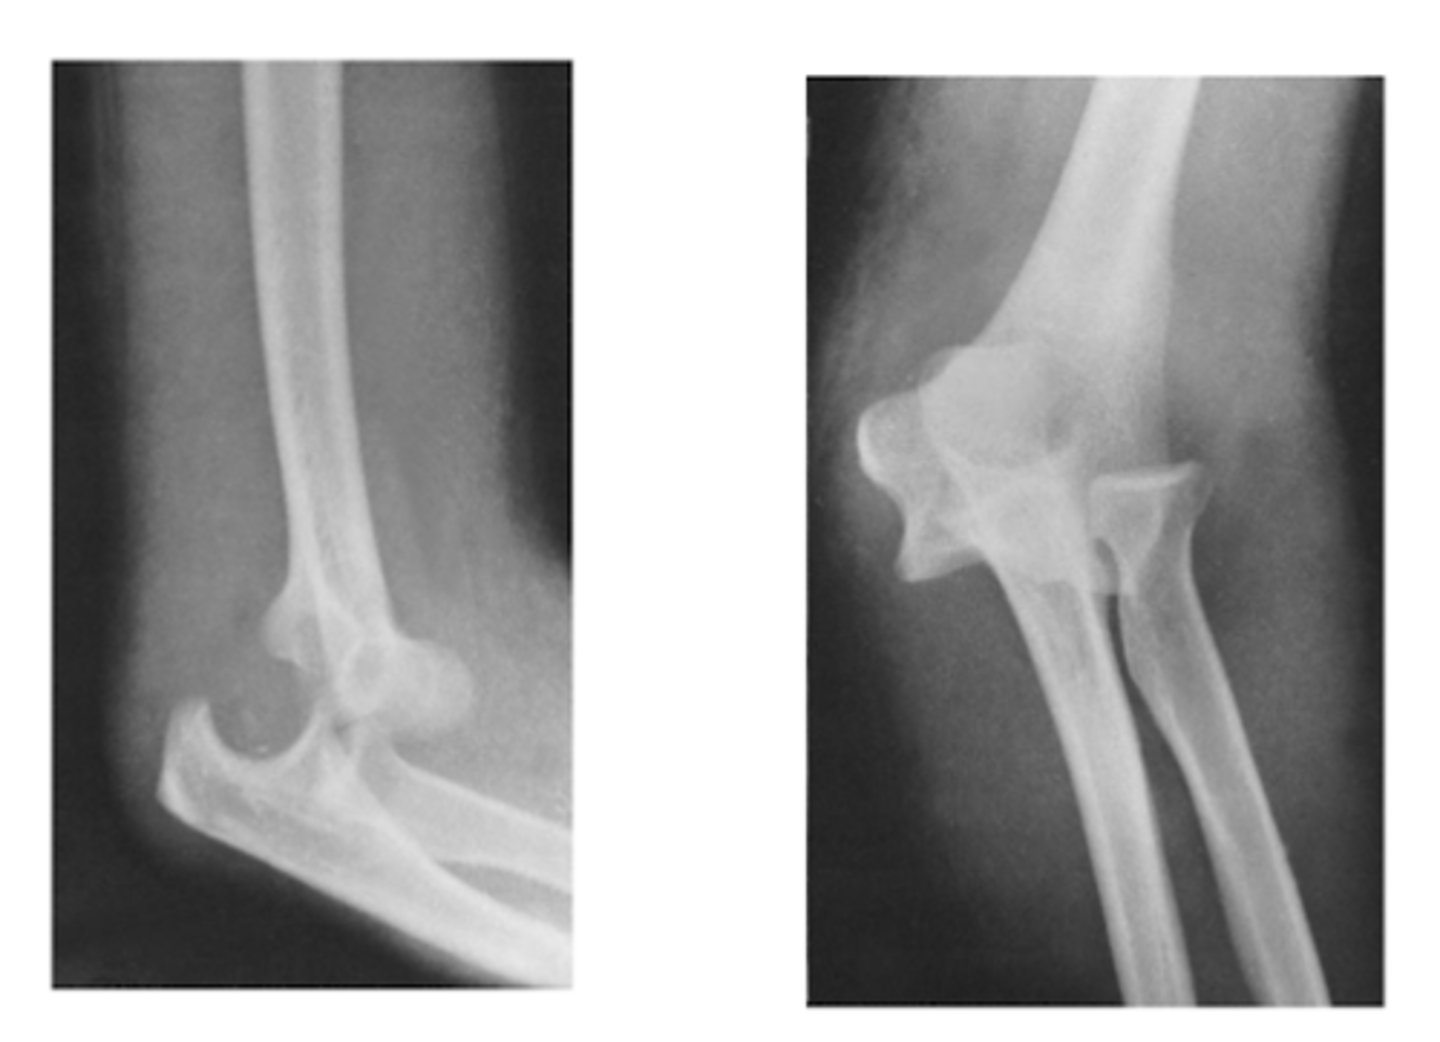

REVIEW: XR of elbow (lateral view)

REVIEW: XR of elbow #2 (lateral view)